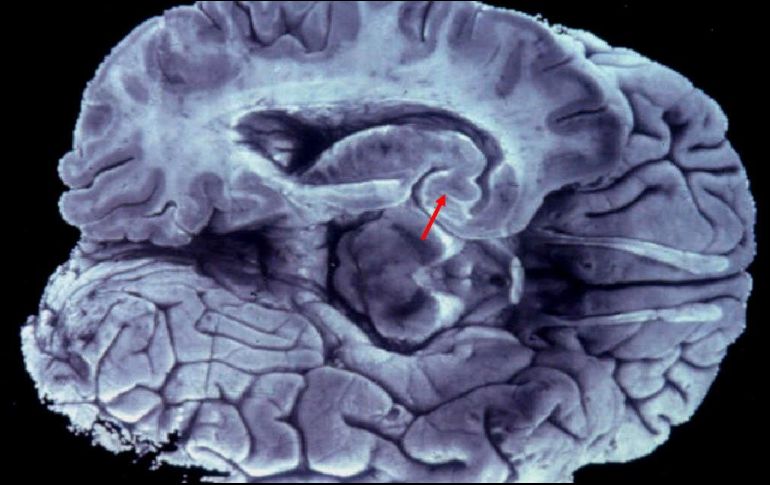

La prueba puede permitir la detección de este padecimiento hasta con 30 años de anticipación. EFE/Archivo